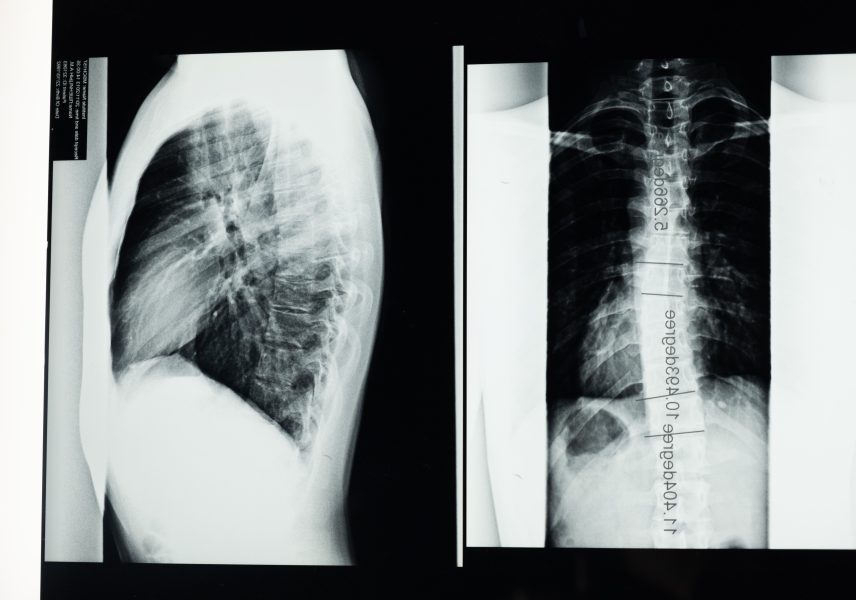

„Днес искам да ви занимая с проблем, който е изключително обвързан с всичко това, което се случва в България. Обвързано е със заболяванията между хората, защото последствията след covid-19 най-често се изразяват в изменения на белия дроб, дихателна недостатъчност и проблеми с дишането. В този ред на мисли, днес ще поговорим малко за хроничната обструктивна белодробна болест (ХОББ). Ще кажем няколко думи и за хроничното белодробно сърце. И така, хроничната обструктивна белодробна болест представлява група от хронични болести, които протичат със затруднения в дишането.Както виждате, тук имаме един нормален бронх. Ето и един, който вече е заболял. Наблюдава се удебеляване на стените. В резултат на това се получава и затруднение в дишането. Тук има макроскопска снимка на бял дроб с нормални алвеоли и с алвеоли, които вече са заболели.Разликата се очевидна…“

В този епизод от Академия Здравитал се говори за хроничната обструктивна белодробна болест, като цялото предаване можете да гледате тук!